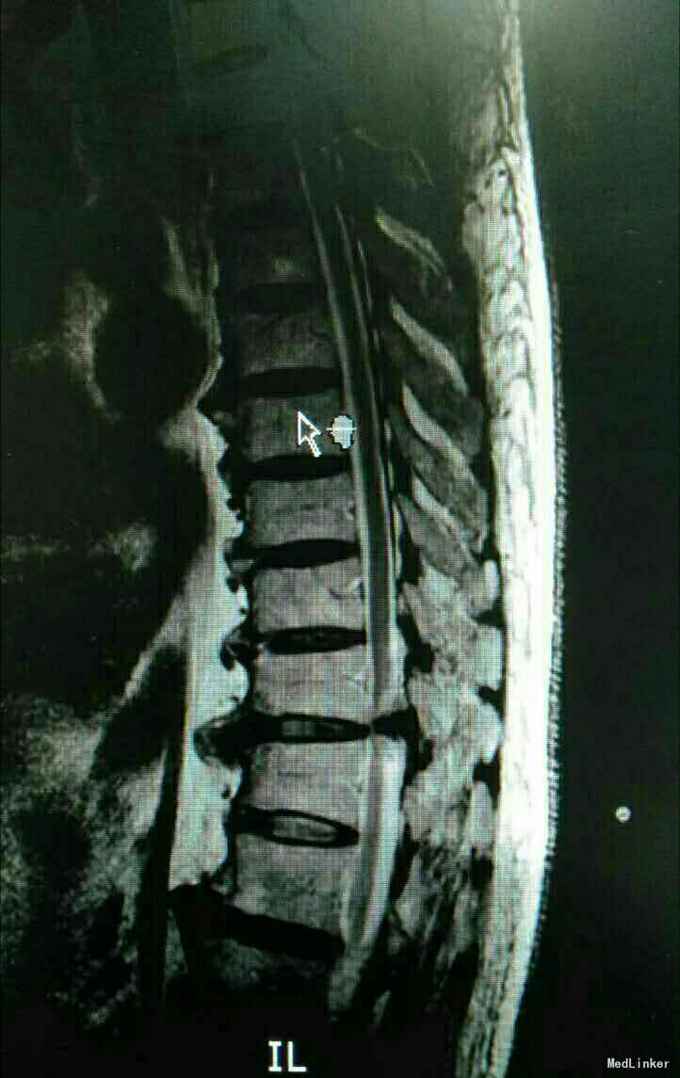

又是严重的胸椎黄韧带骨化,胸10-11、胸11-12。

渐进性双下肢感觉运动障碍10月,大小便障碍10天。